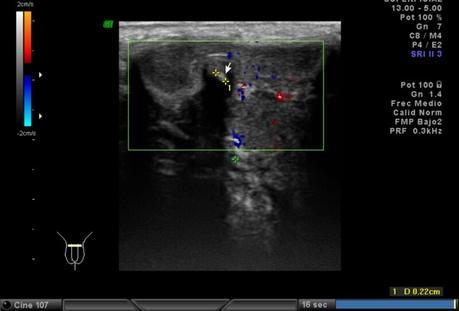

A nivel de base del pené, entre los cuerpos cavernoso y esponjoso en su porción central se observa la presencia de calcificación, que mide 2.2 mm. En tercio distal del pené, a nivel de cuerpos cavernosos con presencia de calcificación que mide 1.8 mm.

Trayectos vasculares conservados.

A NIVEL DE BASE Y TERCIO DISTAL DEL PENÉ, EN CUERPOS CAVERNOSOS CON PLACAS A RELACIÓN A ENFERMEDAD PEYRONIE.